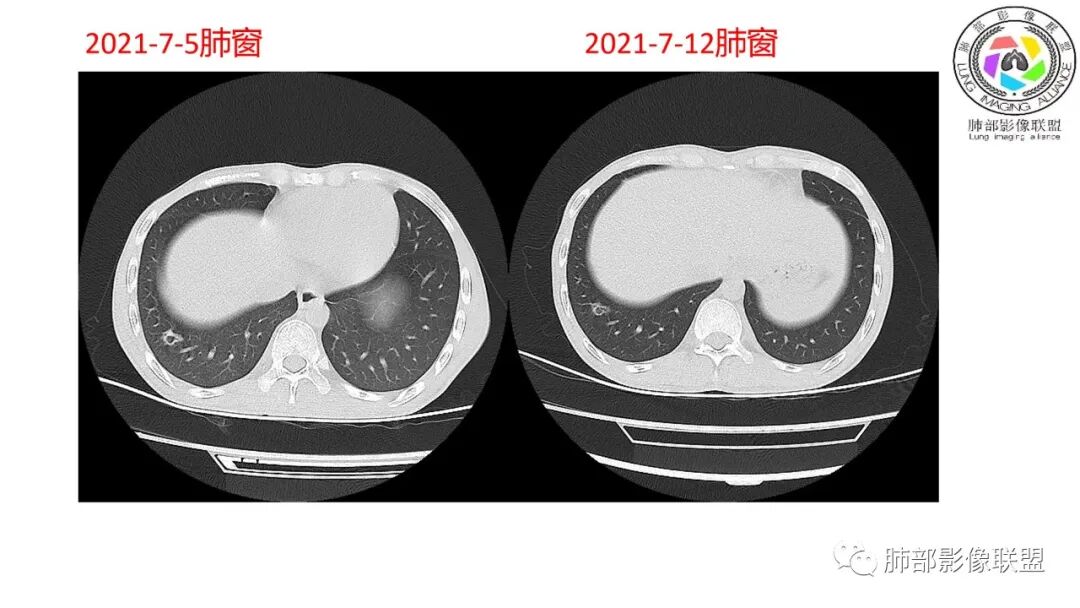

南边:对侧?

南边:12日好一些

南边:支持炎性,结合病史,马尼首选

影像与临床:1.青年男性,HlV阳性,颜面部皮疹(未提供皮疹图像)、发热(高热),实验室CRP、PCT高,T-Spot阴性。2.右肺下叶空洞结节,壁厚不均,边界清楚,其内线状影,未见液平及钙化,未见卫星灶,纵隔淋巴结增大,双侧腋窝见增大淋巴结。心腔内低密度提示贫血可能。肝脾影增大,未见结节影及块影。腹膜后见多发增大淋巴结。

综合分析:本例肺部影像学改变并不具有特征性,空洞性病灶须与多种疾病鉴别,但年轻HIV阳性患者,高热,皮疹,肝脾增大,纵隔、腋窝、腹膜后见多发增大淋巴结等都强烈提示马尔尼菲篮状菌感染的可能性。